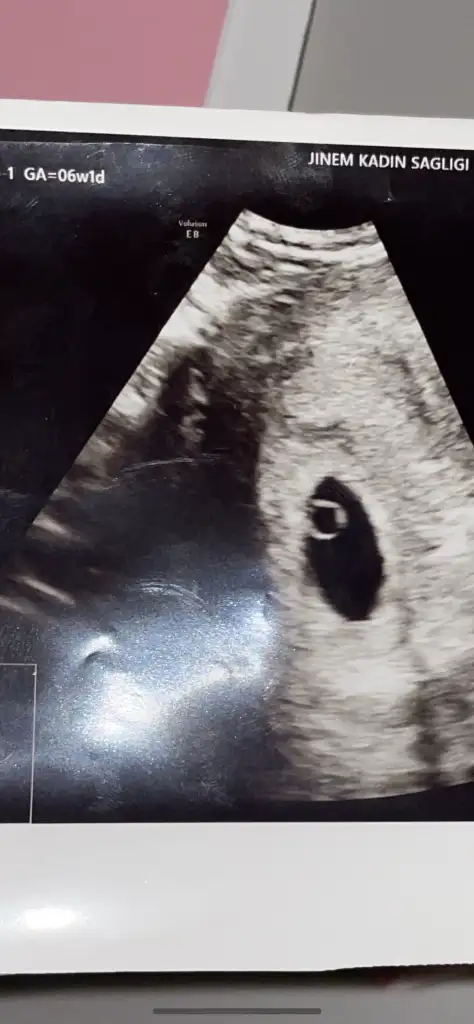

İlk ultrason karından 6 veya 7 haftalıktu kız mı erkek mi :) bu da 10+6 iken